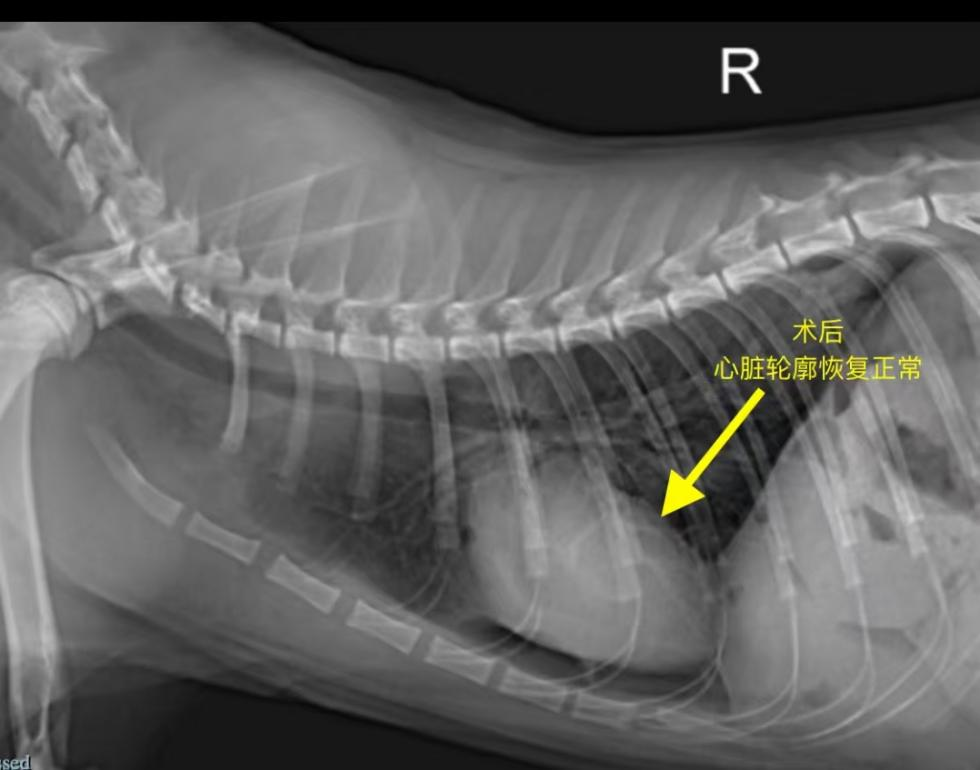

The liver was carefully separated, and the diaphragmatic defect was sutured and repaired, restoring normal thoracoabdominal anatomy.